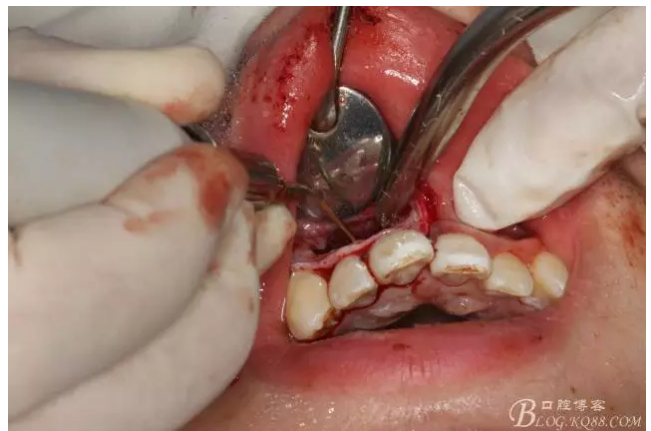

圖2.根管治療術(shù)后直接局部 麻醉下切開、翻瓣,發(fā)現(xiàn)12唇側(cè)骨壁有綠豆大小骨缺損

圖3.依缺損部位為中心,逐漸去骨,完整暴露出囊壁。

圖4.摘除囊壁后形成的巨大骨腔